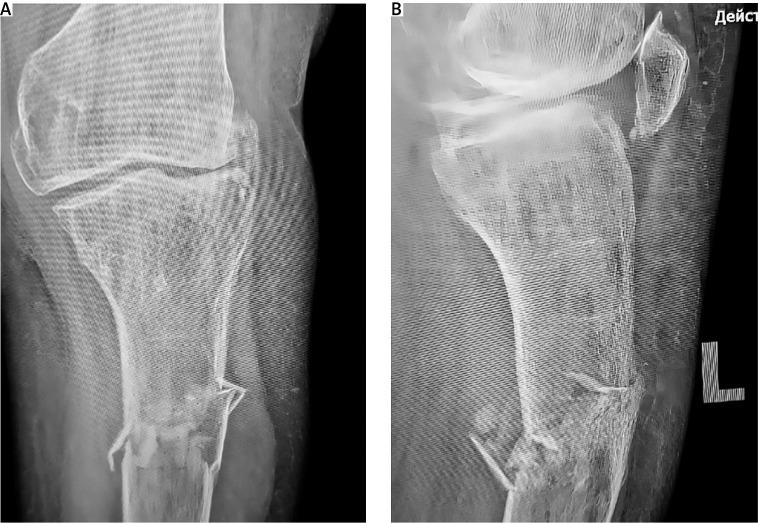

骨折延迟愈合是骨科临床常见的并发症,在骨质疏松患者中尤为常见。再生医学的进展,包括基质血管成分中的间充质干细胞(MSCs),为应对这一挑战引入了新的治疗方法。本病例描述了一名患有绝经后骨质疏松症和左下肢先天性异常的患者,其胫骨近端骨折并伴有骨折块移位。开始进行骨质疏松治疗,并采用外固定和加压处理骨折。尽管在八个月期间骨密度有所改善,但影像学评估显示没有骨折愈合的迹象。因此,在骨折部位进行了间充质干细胞局部给药并结合针刺治疗,随后进行了一系列自体浓缩血浆(ACP)注射。三个月内观察到骨痂形成的影像学迹象,最终在再生治疗开始六个月后实现了骨折完全愈合。尽管我们诊所的病例数量有限,无法就骨折愈合的主要促成因素得出明确结论,但现有文献表明,高浓度动员骨折部位的内源性资源可促进组织再生。体育活动和辅助药物治疗进一步促进了这一过程。整合间充质干细胞和ACP衍生生长因子的再生治疗是一种有前景的辅助方法,用于管理全身性骨质疏松患者的骨折并发症。该策略有可能促进骨愈合,同时有可能延迟甚至避免更具侵入性的手术干预的需要。